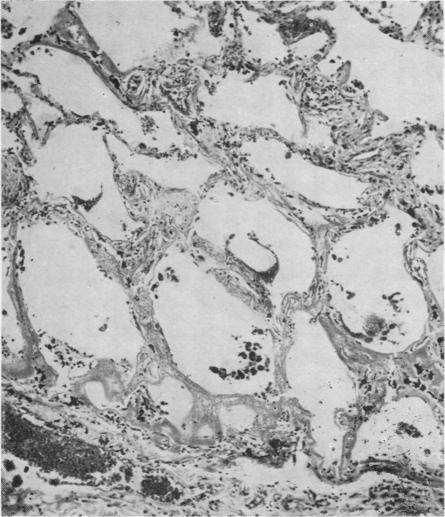

Primary amyloidosis: a review.

J Clin Pathol. 1956 Aug;9(3):187-211. doi: 10.1136/jcp.9.3.187.